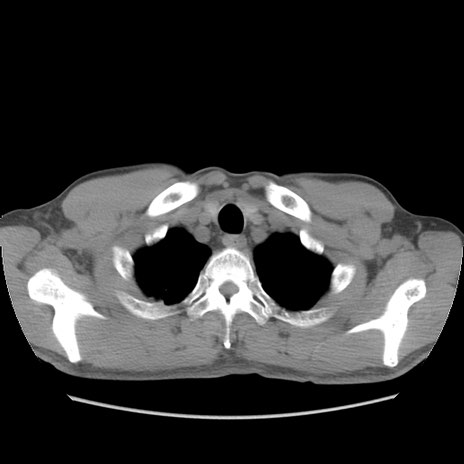

症例56 CT(横断像)

脂肪ウインドウ